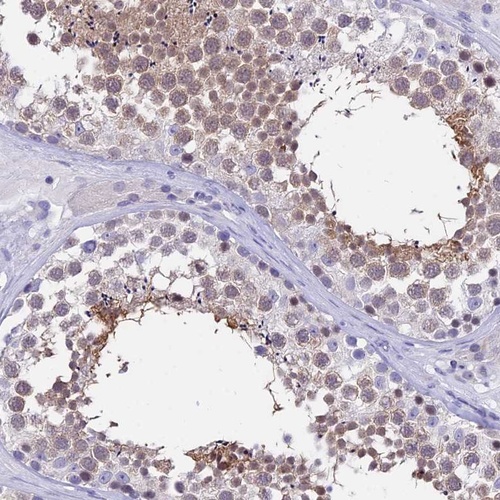

Immunohistochemical staining of human testis shows moderate cytoplasmic and nuclear positivity in cells of seminiferus ducts.